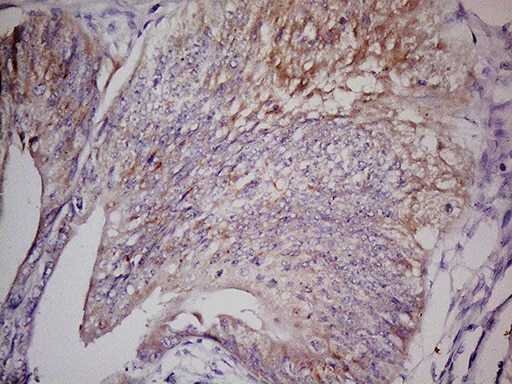

- Immunohistochemical staining of paraffin-embedded human colon cancer using mouse anti-LGR5 clone UMAB212 (UM800104) at 1:400 with GBI Polink2 Broad HRP DAB detection kit (D22-110); pretreatment of tissue prior to stain with heat-induced epitope retrieval buffer from GBI Labs TEE pH 9.0 (B21-100)using pressure chamber for 3 minutes at 110°C is required for optimal staining. Shown here strong cytoplamic tumor cells.